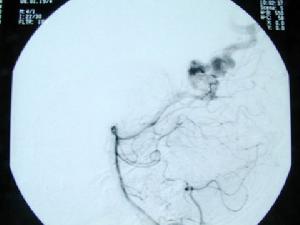

7、選擇性全腦血管造影(DSA)可了解AVM的部位、供血動脈、畸形血管團大小以及引流靜脈,了解是否伴有動脈瘤、靜脈瘤、動靜脈瘺及腦盜血情況。必要時加做頸外動脈造影,以了解是否有頸外動脈參與供血。

⑥腦血管造影。是診斷動靜脈畸形的重要手段。是必須進行的檢查方法。不僅能確定診斷而且還為治療提供依據。造影常顯示不規則曲張扭纏的畸形血管團,並可顯示供血動脈和引流靜脈。引流靜脈常在動脈期即可過早顯影。但仍有一部分小的或隱匿型動靜脈畸形不能被造影發現(約11%)。數字減影、放大造影、連續攝片、立體血管造影等更有助於診斷。